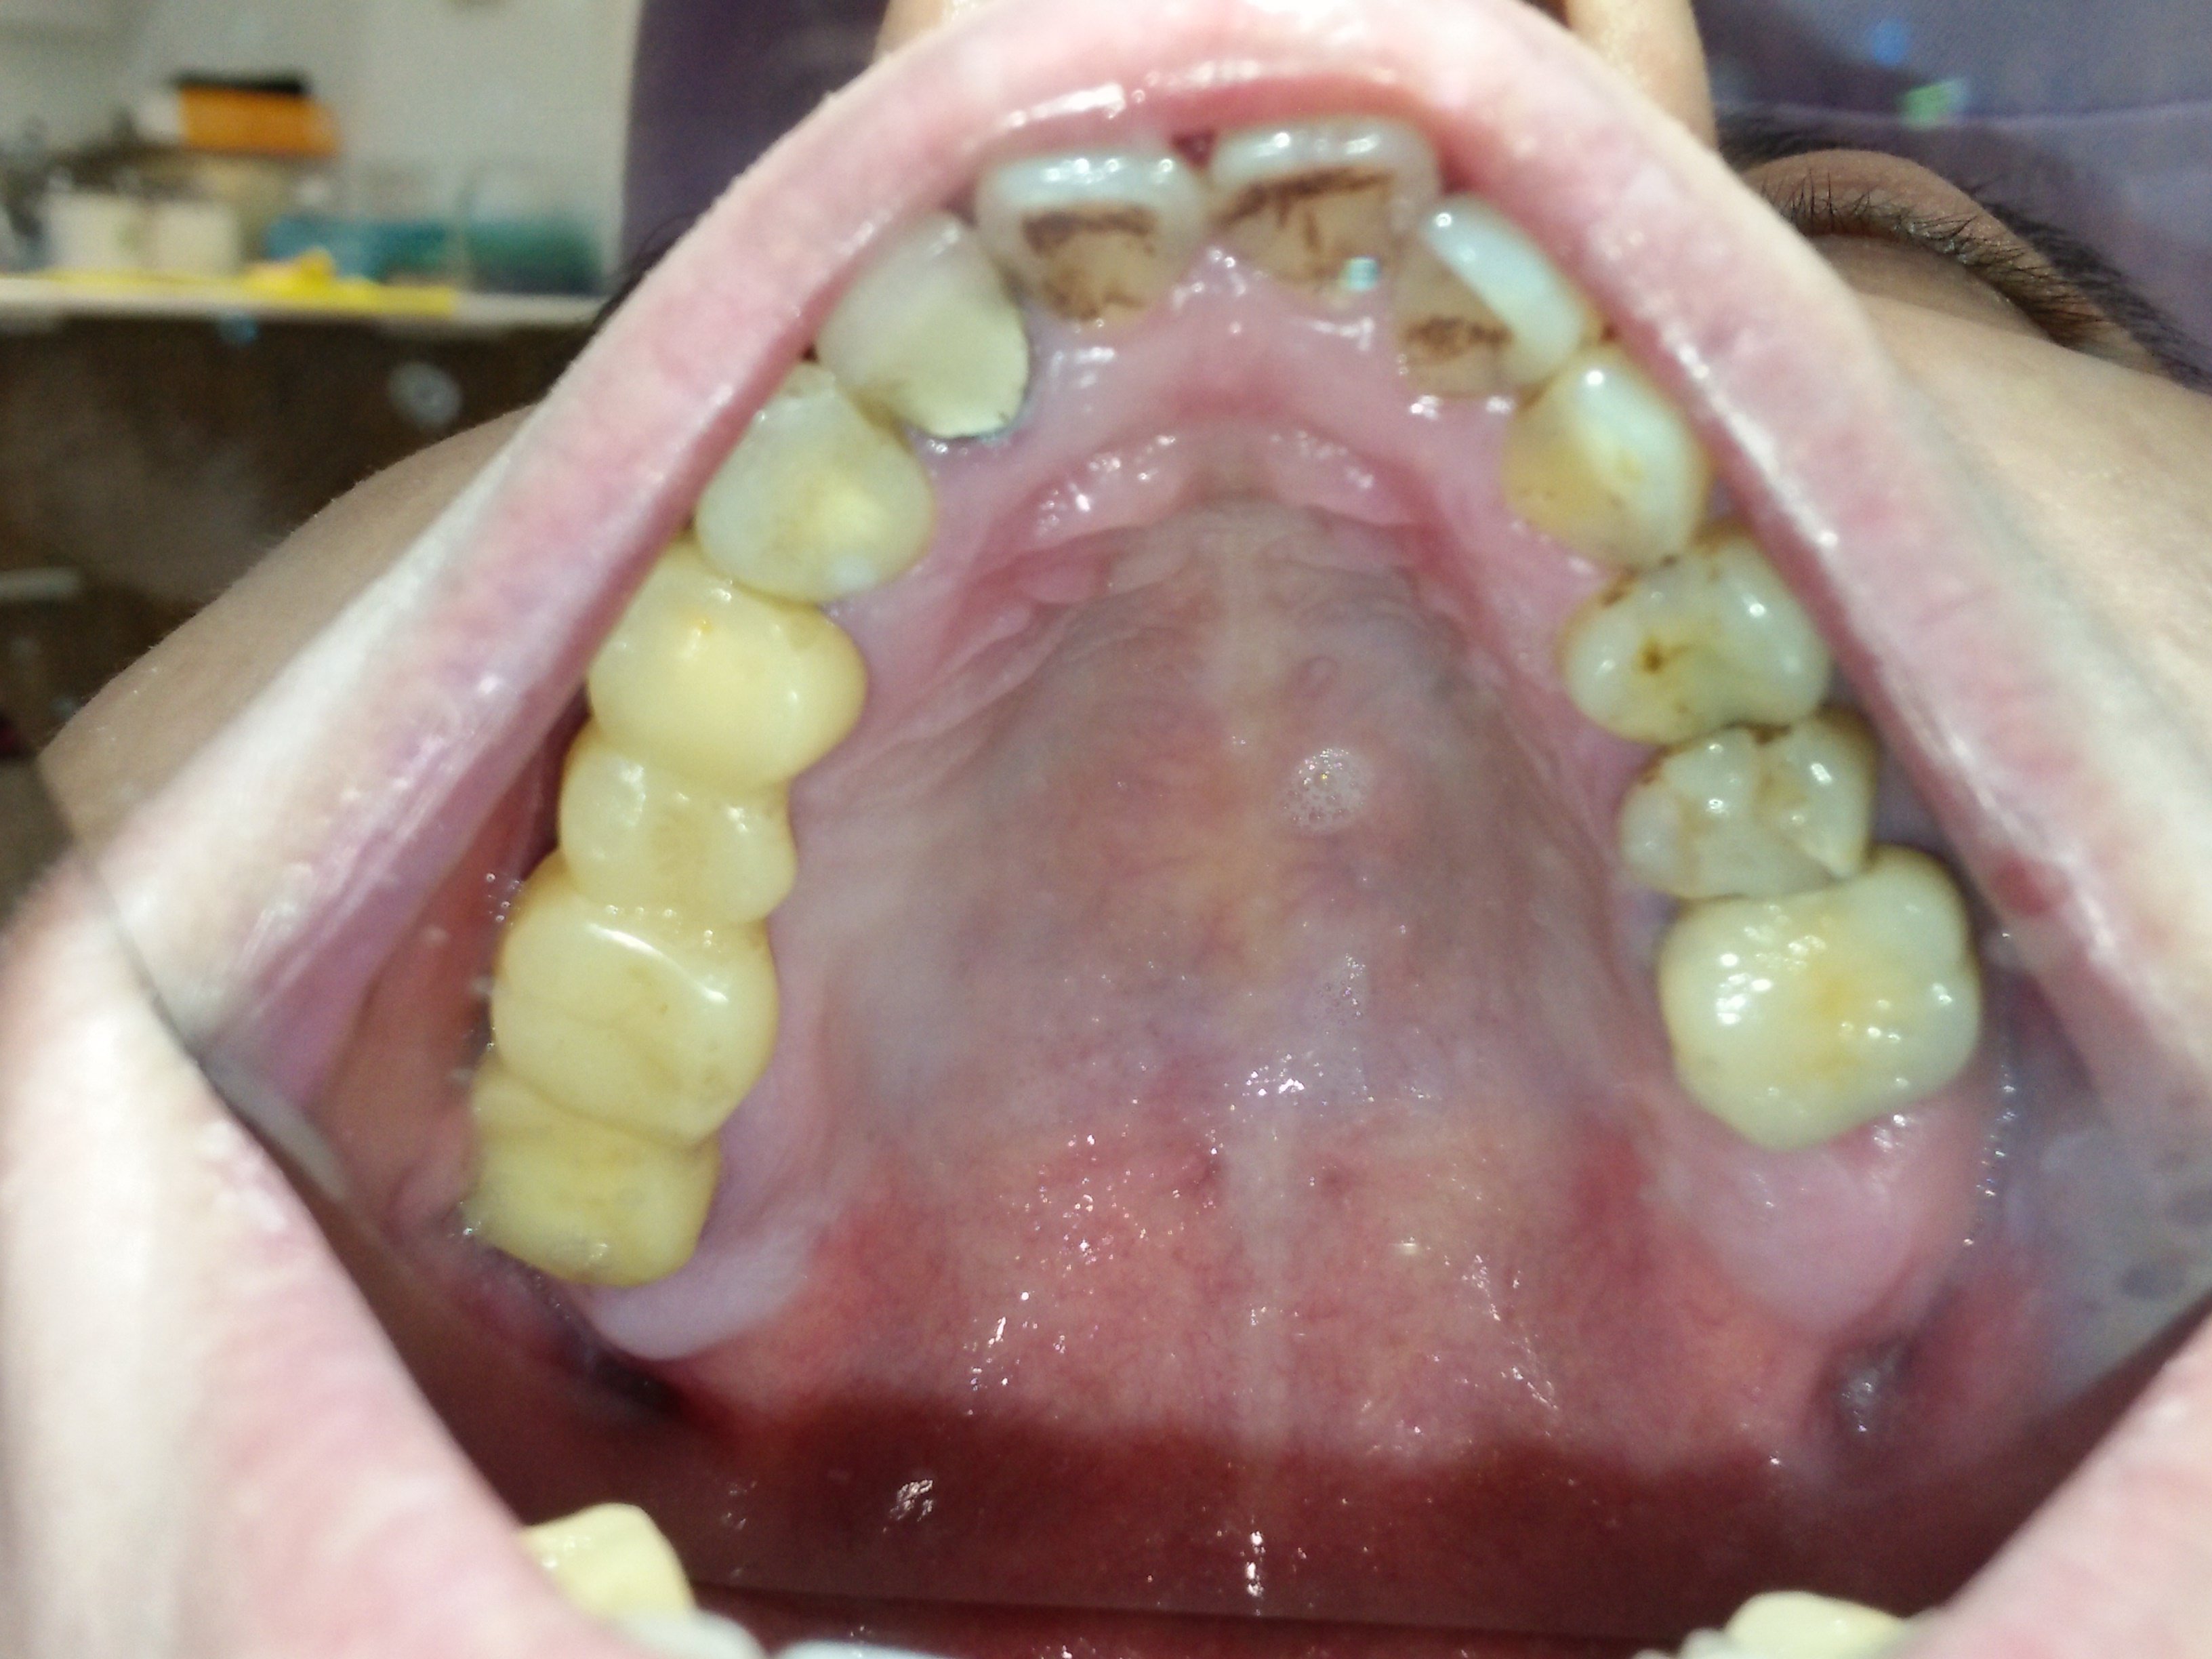

這才發現原來補骨醫師技術有別,不是有補就好,蛀牙也不是一再重複處理讓牙齒神經反覆受刺激;需要先處理咬合、排列的問題,再將缺牙、蛀牙和前牙美觀合併處理,不但解決了牙縫塞東西造成蛀牙不斷,也讓牙齒排列改變改變外觀。

補骨後再植牙,讓牙齒地基有足夠的骨本,也讓自己擺脫總是在做假牙或做假牙的路上的命運。

改變觀念,跟上世界潮流的治療腳步,您可以擁有與展現與眾不同的笑容,讓人生更加精采!